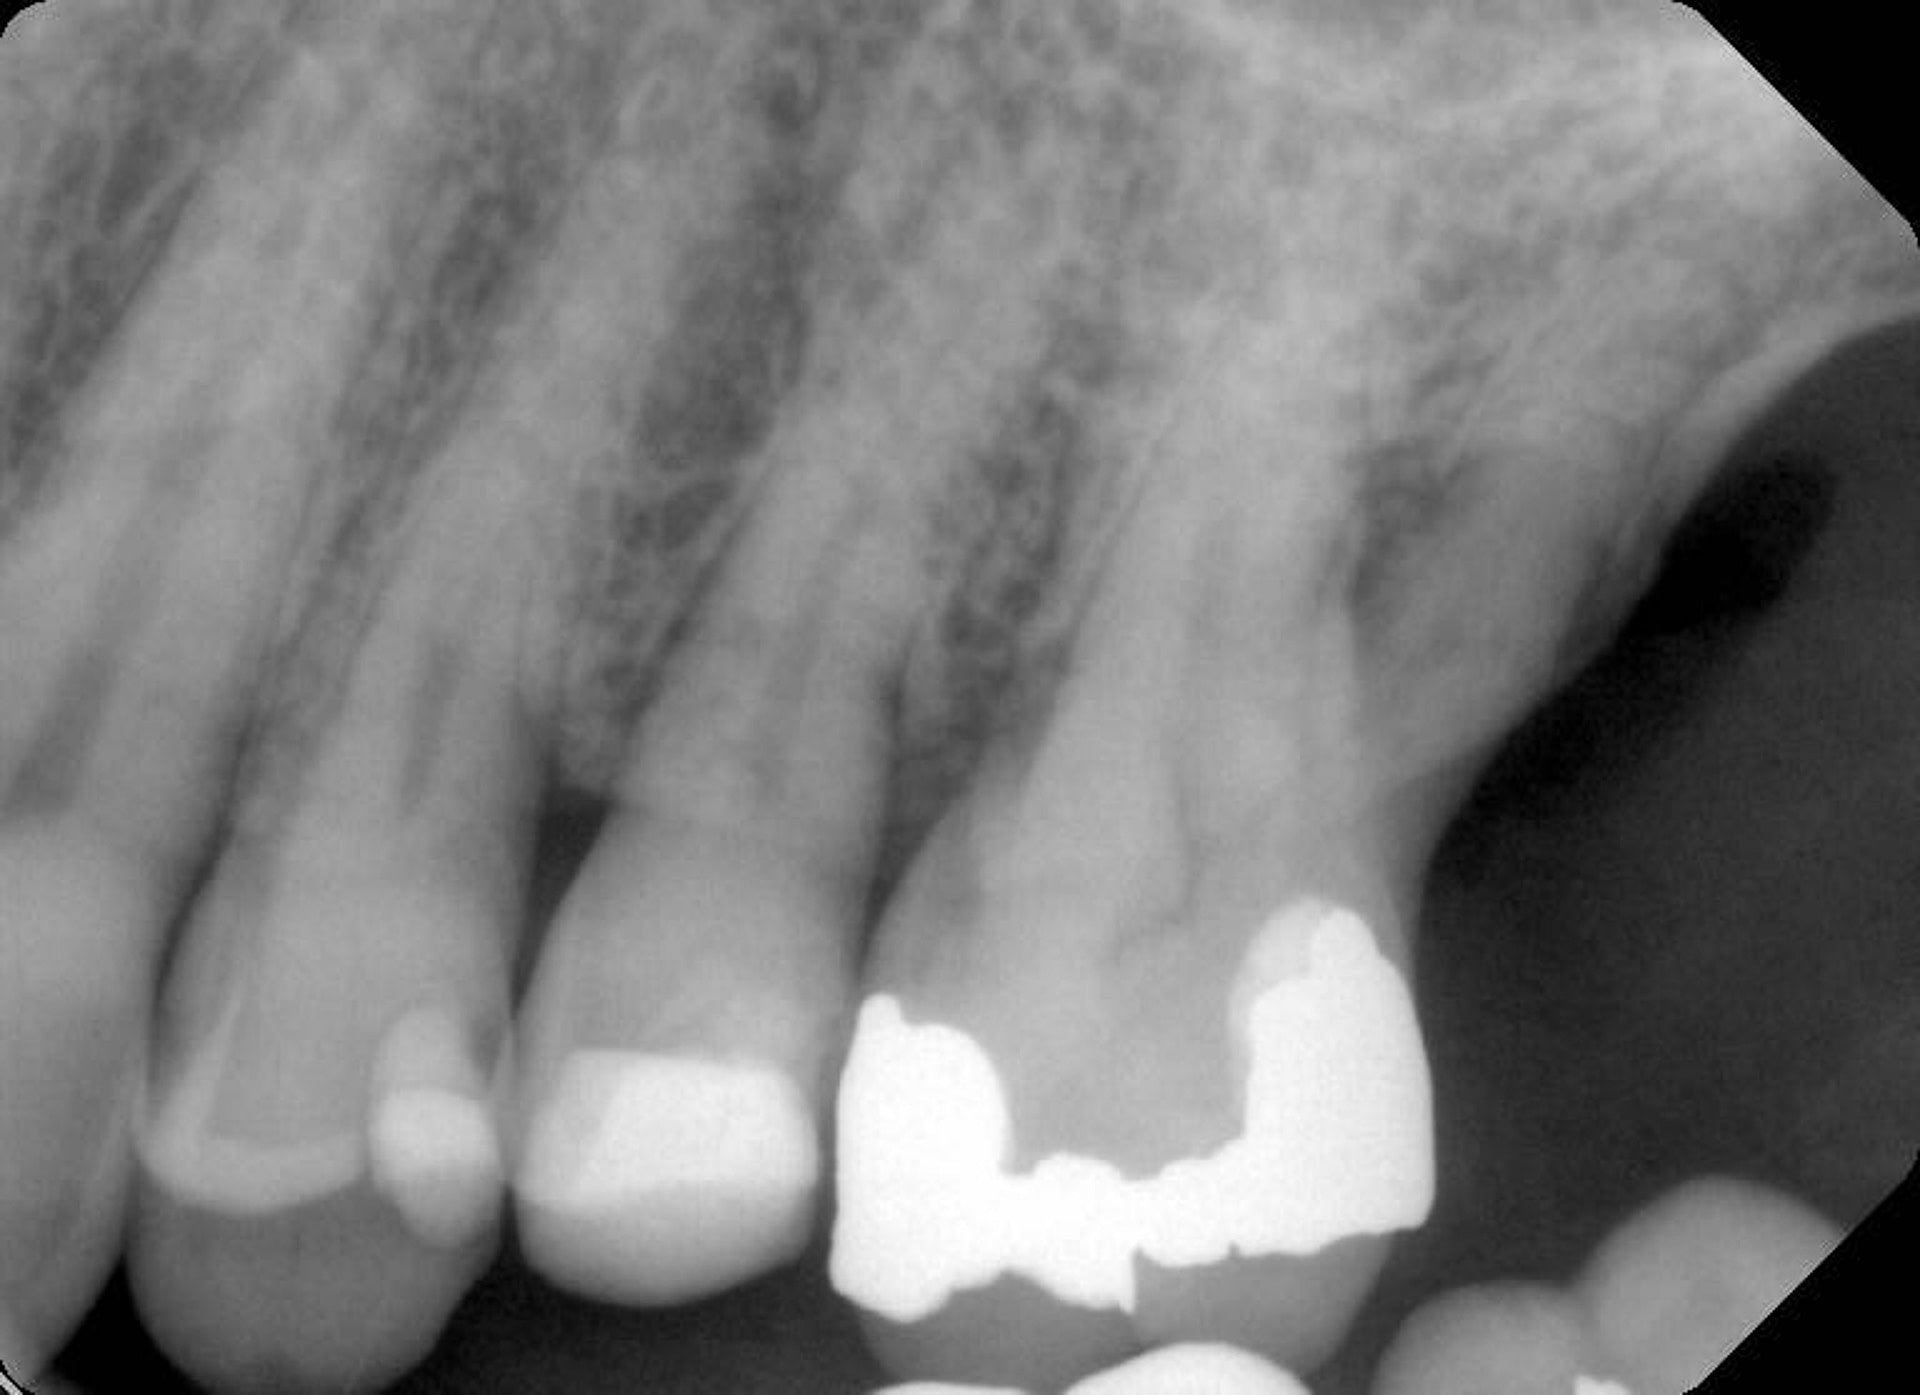

Over the years, the patient had experienced multiple cracked teeth, which had led to various complications and treatments. In 2021, the patient reported hearing a loud crack while eating, after which tooth 24 became tender to biting pressure.

Upon examination by his previous dentist, a vertical root fracture was diagnosed, necessitating a surgical extraction. The procedure, which involved removing the buccal cortical bone, left the patient with a bony defect in the area of the extracted tooth.

To better understand the patient's overall dental health, a full mouth CBCT scan was taken, confirming the presence of a bony defect in the area where tooth 24 had been surgically extracted.